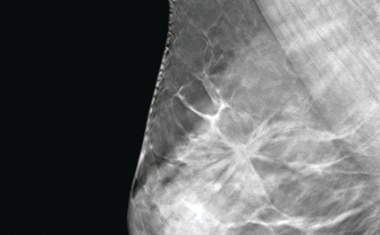

Moment, fehlt da nicht noch etwas? Die Medizinische Technologin verlässt den Raum, um die Röntgenaufnahme vom Brustkorb zu starten, aber dieses schwere Teil von den vorigen Malen ist noch gar nicht um die Hüfte gelegt worden.